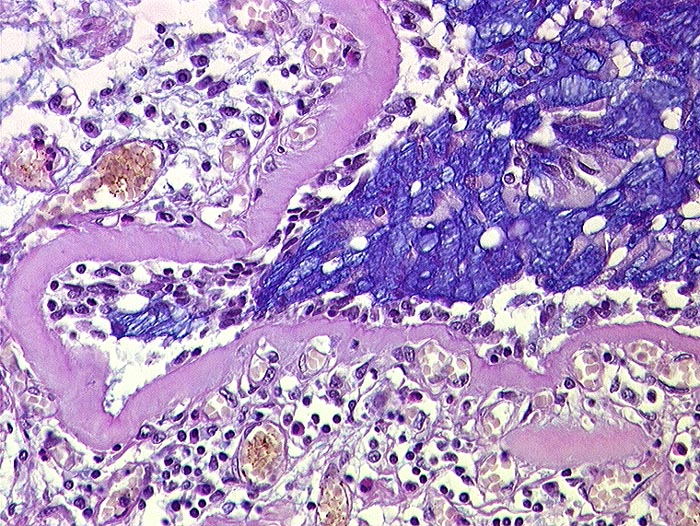

Asthma bronchiale

Bronchiolus mit Becherzellhyperplasie, starker Verdickung der Basalmembran und subepithelialem lymphoplasmazellulärem Entzündungsinfiltrat unter Beteiligung eosinophiler Granulozyten.

Tod im Asthmaanfall bei bekanntem Asthma bronchiale.